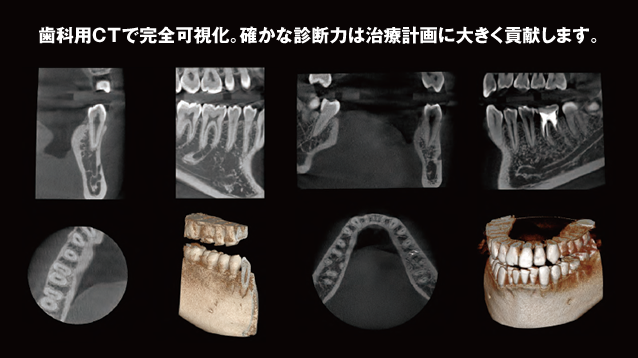

インプラント治療を行うには、顎の骨の形、顎の骨の中にある神経の位置など事前に把握しなければなりません。過去において一般的な歯科用のレントゲンで顎の状態を確認していましたが、レントゲンでは二次元的な情報しか得られませんでした。しかし、近年では歯科用や医科用にCTが普及し、顎の状態、神経の位置など、インプラント治療に必要な情報をより詳しく把握できるようになりました。これにより、どこに、何本のインプラントを埋入すればよいのかを決定することができます。それに伴い術範囲も小さく最低限の外科治的処置で治療が可能となっています。

CTデータを使用することで、インプラント治療部位の骨形態や骨の内部構造、さらにはその周辺の構造までが三次元に把握できるようになっています